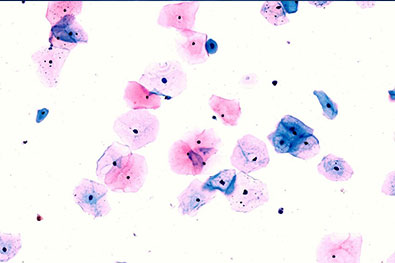

Specialized Cervical Cytology Database

Our dedicated Cervical Cytology database is designed to support AI-driven screening and diagnostic research. It includes a structured and validated collection of cytology cases covering the complete disease spectrum.

- Normal cytology cases

- Premalignant lesions (LSIL / HSIL)

- Malignant cytology cases

- Conventional Pap smears

- Liquid-Based Cytology (LBC) smears

- High-resolution Whole Slide Images (WSIs)

- AI-ready structured datasets